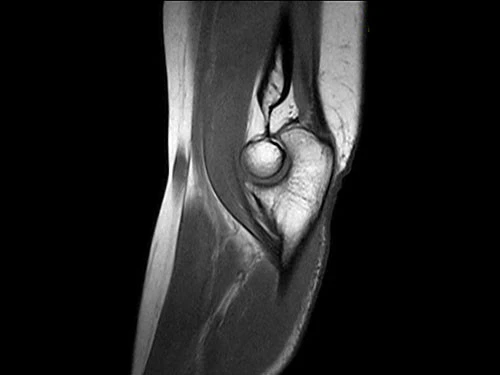

Система Esaote для динамической МРТ способна выявлять скрытые ущемления, которые трудно или невозможно обнаружить с помощью стандартной статической МРТ. Функциональная оценка обеспечивает дополнительный инструмент для более качественного обслуживания пациентов, особенно в спортивной медицине высокого уровня.

O-scan Впечатляющее качество изображения

Высокопроизводительная система O-scan обеспечивает впечатляющее качество визуализации и экономичное функционирование с низким порогом рентабельности: с системой может работать только один оператор.